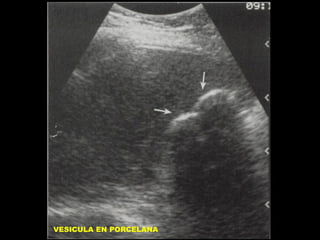

VESICULA EN PORCELANA

VESICULA ESCLEROATROFICA

INCIDENCIA: 0,06 A 0,8 %

ASOCIADA A LITIASIS VESIC. EN 95% DE CASOS

MAS FREC. EN SEXO F: 5:1

HIPOTESIS:

CALCIFICACION DISTROFICA POR INF. CRONICA

Y COMPROMISO DEL FLUJO SANGUINEO.

IRRITACION CRONICA POR CALCULOS

OBSTRUCCION CRONICA DEL CISTICO O CB

RELACION CON CA: 11 A 33 %